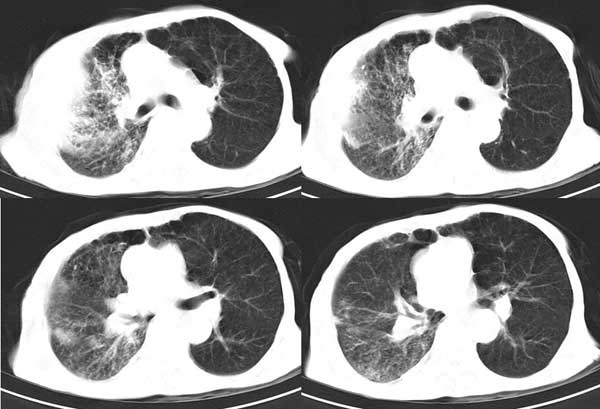

患者男,81岁,咳喘10余年,继往结核病史,发现胸部体表肿物(具体时间不详)就诊

右侧胸廓塌陷。右前上外侧胸壁软组织肿块,其内见有低密度影,肋骨呈溶骨性表现。右肺上叶见大量的间质纤维化表现。右侧膈肌上抬。

患者男,81岁,咳喘10余年,继往结核病史,发现胸部体表肿物

考虑:1、继发性结核,右结核性胸膜炎伴胸壁结核性感染

2、右侧胸壁恶性肿瘤。

肺尖巨大肿块影阴,胸壁受侵肋骨破坏,肿块密度不均且穿破胸壁入皮下,应该是:肺上沟癌;由于肺内有斑片状播散病灶,因此不排除胸壁结核。

患者男,81岁,咳喘10余年,继往结核病史,发现胸部体表肿物。

考虑:1 右侧胸壁恶性肿瘤(多考虑:胸膜间皮瘤)。

2 继发性结核,右结核性胸膜炎伴胸壁结核性感染。